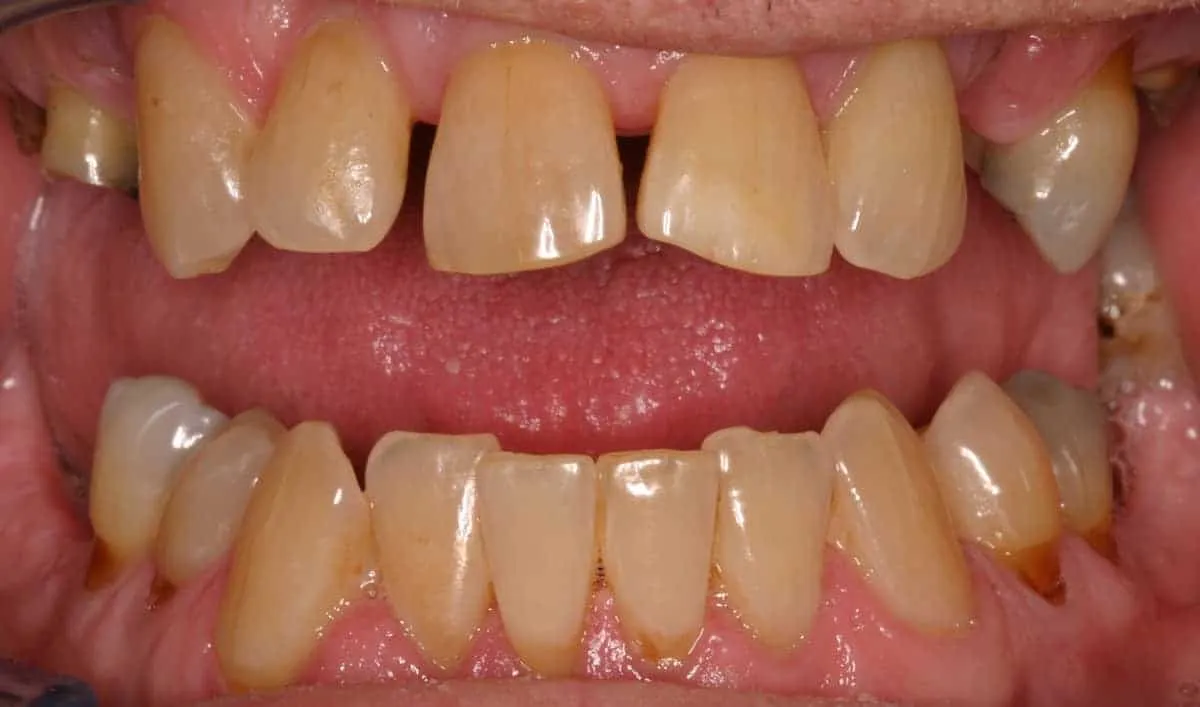

Before: Failed upper remaining teeth requiring removal. Patient elected to proceed with Phase I immediate complete denture therapy with the view toward phase II implant therapy.